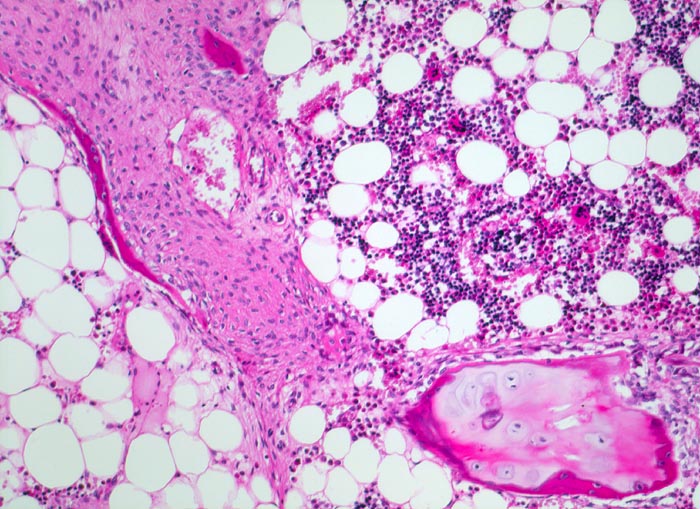

Osteogenesis imperfecta: Fraktur

Knochen, Rippe

Ausschnitt aus der Frakturzone mit metaplastischem Bindegewebe und hyalinem Knorpel.

Tod an Rechtsherzversagen bei Cor pulmonale. Multiple, zum Teil nicht ganz frische Frakturen vorwiegend der Rippen mit ausgeprägter Deformierung des Thorax und des übrigen Skeletts. Generalisierte Osteopenie. Kyphoskoliose. Multiple Knochenmarkembolien der Lunge.

Glasknochenkrankheit, pulmonale arterielle Hypertonie

Histologie

100